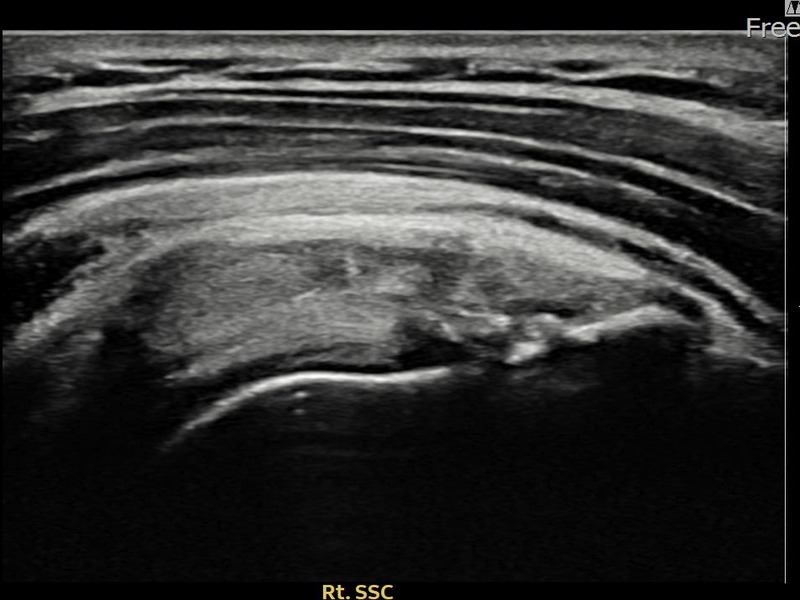

유ㅇㅇ님 · 우측 견갑하근건 관절면측 부분파열

우측 어깨 전방 통증과 팔 내회전 제한으로 내원하셨습니다. 초음파 검사에서 견갑하근건 관절면측 부분파열이 확인되었으며, 어깨인대 축소봉합술 후 힘줄 구조적 안정화가 이루어졌습니다.

유ㅇㅇ님 · 우측 견갑하근건 부분파열

우측 어깨 전방 통증과 팔 들어 올리기 어려움으로 내원하셨습니다. 초음파 검사에서 견갑하근건 부분파열이 확인되었으며, 어깨인대 축소봉합술 후 힘줄 연속성이 회복되고 어깨 기능이 정상화되었습니다.